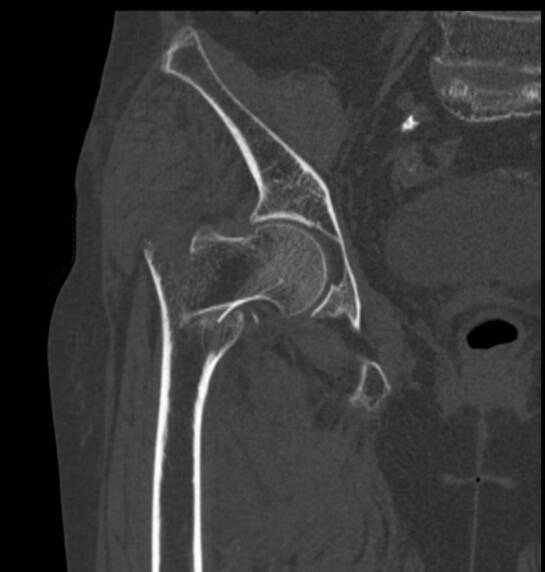

今年90岁的王奶奶(化名),因在家中不慎摔倒,导致右侧髋部剧烈疼痛、无法活动,被紧急送至中心。经检查,确诊为“右侧股骨粗隆间骨折”。对于年轻人而言,这样的骨折可通过手术获得良好恢复,但对于已届鲐背之年的王奶奶来说,却是一次生死考验。

在麻醉科金延武主任团队的精准护航下,采用了神经阻滞麻醉方式,全程严密监测王奶奶的生命体征。骨科高红伟主任团队凭借丰富的经验,选择了创伤小、出血少、固定可靠的微创手术方案。术中在C型臂透视下牵引复位骨折,通过几个3-5cm切口,轻柔、迅速、精准地置入大小合适的股骨髓内钉,力求将手术创伤降至最低。整个手术过程如行云流水,仅用一小时便顺利完成,出血量被控制在了极低水平。